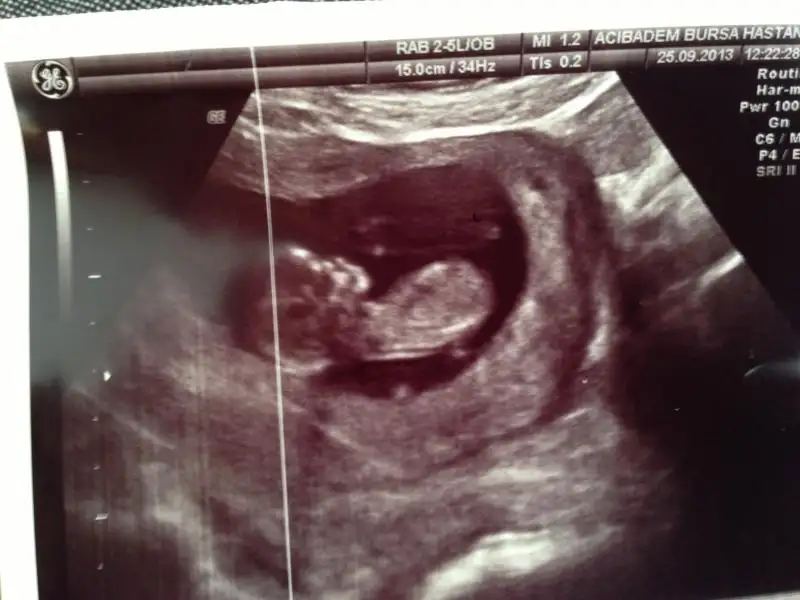

Eki Görüntüle 814373 Eki Görüntüle 814375 Eki Görüntüle 814378 Eki Görüntüle 814381 merhaba arkadaşlar bende aranıza yeni katıldım.12 haftalık hamileyim konuyu okuyunca dayanamadım yükledim resimleri.bakarmısınız sizce ne olabilir bebişimin cinsiyeti

9+3 günlük..... 10 haftalık demişti doktor........umarım belli oluyodur :))))